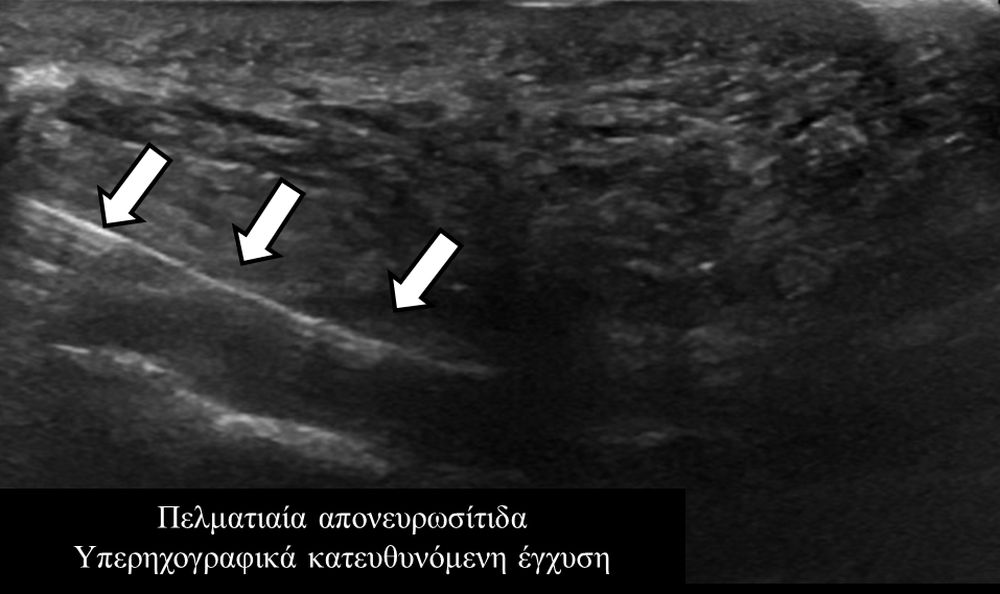

Υπό συνεχή υπερηχογραφική παρακολούθηση είναι δυνατόν να πραγματοποιηθούν κατευθυνόμενες εγχύσεις σε ορθοπαιδικές και ρευματολογικές παθήσεις. Αρχικά εντοπίζεται η παθολογική περιοχή και στη συνέχεια εξετάζεται η βέλτιστη οδός προσπέλασης. Ακολούθως γίνεται υπό άμεση και συνεχή υπερηχογραφική παρακολούθηση οι απαραίτητοι χειρισμοί και έγχυση φαρμάκων ακριβώς στη θέση της βλάβης.

Εχει αποδειχθεί ότι με την υπερηχογραφική καθοδήγηση εξασφαλίζεται:

- μεγαλύτερη ακρίβεια και αποτελεσματικότητα (αφού η έγχυση/θεραπεία γίνεται ακριβώς στηνπαθολογική περιοχή)

- καλύτερη ανοχή από τον ασθενή (λιγότεροι τραυματικοί χειρισμοί αφού έχουμε άμεση και συνεχή εποπτεία της βελόνας)

- μεγαλύτερη ασφάλεια (αποφυγή τρώσης νεύρων, αγγείων, γειτονικών ανατομικών δομών).

- σε πελματιαία απονευρωσίτιδα